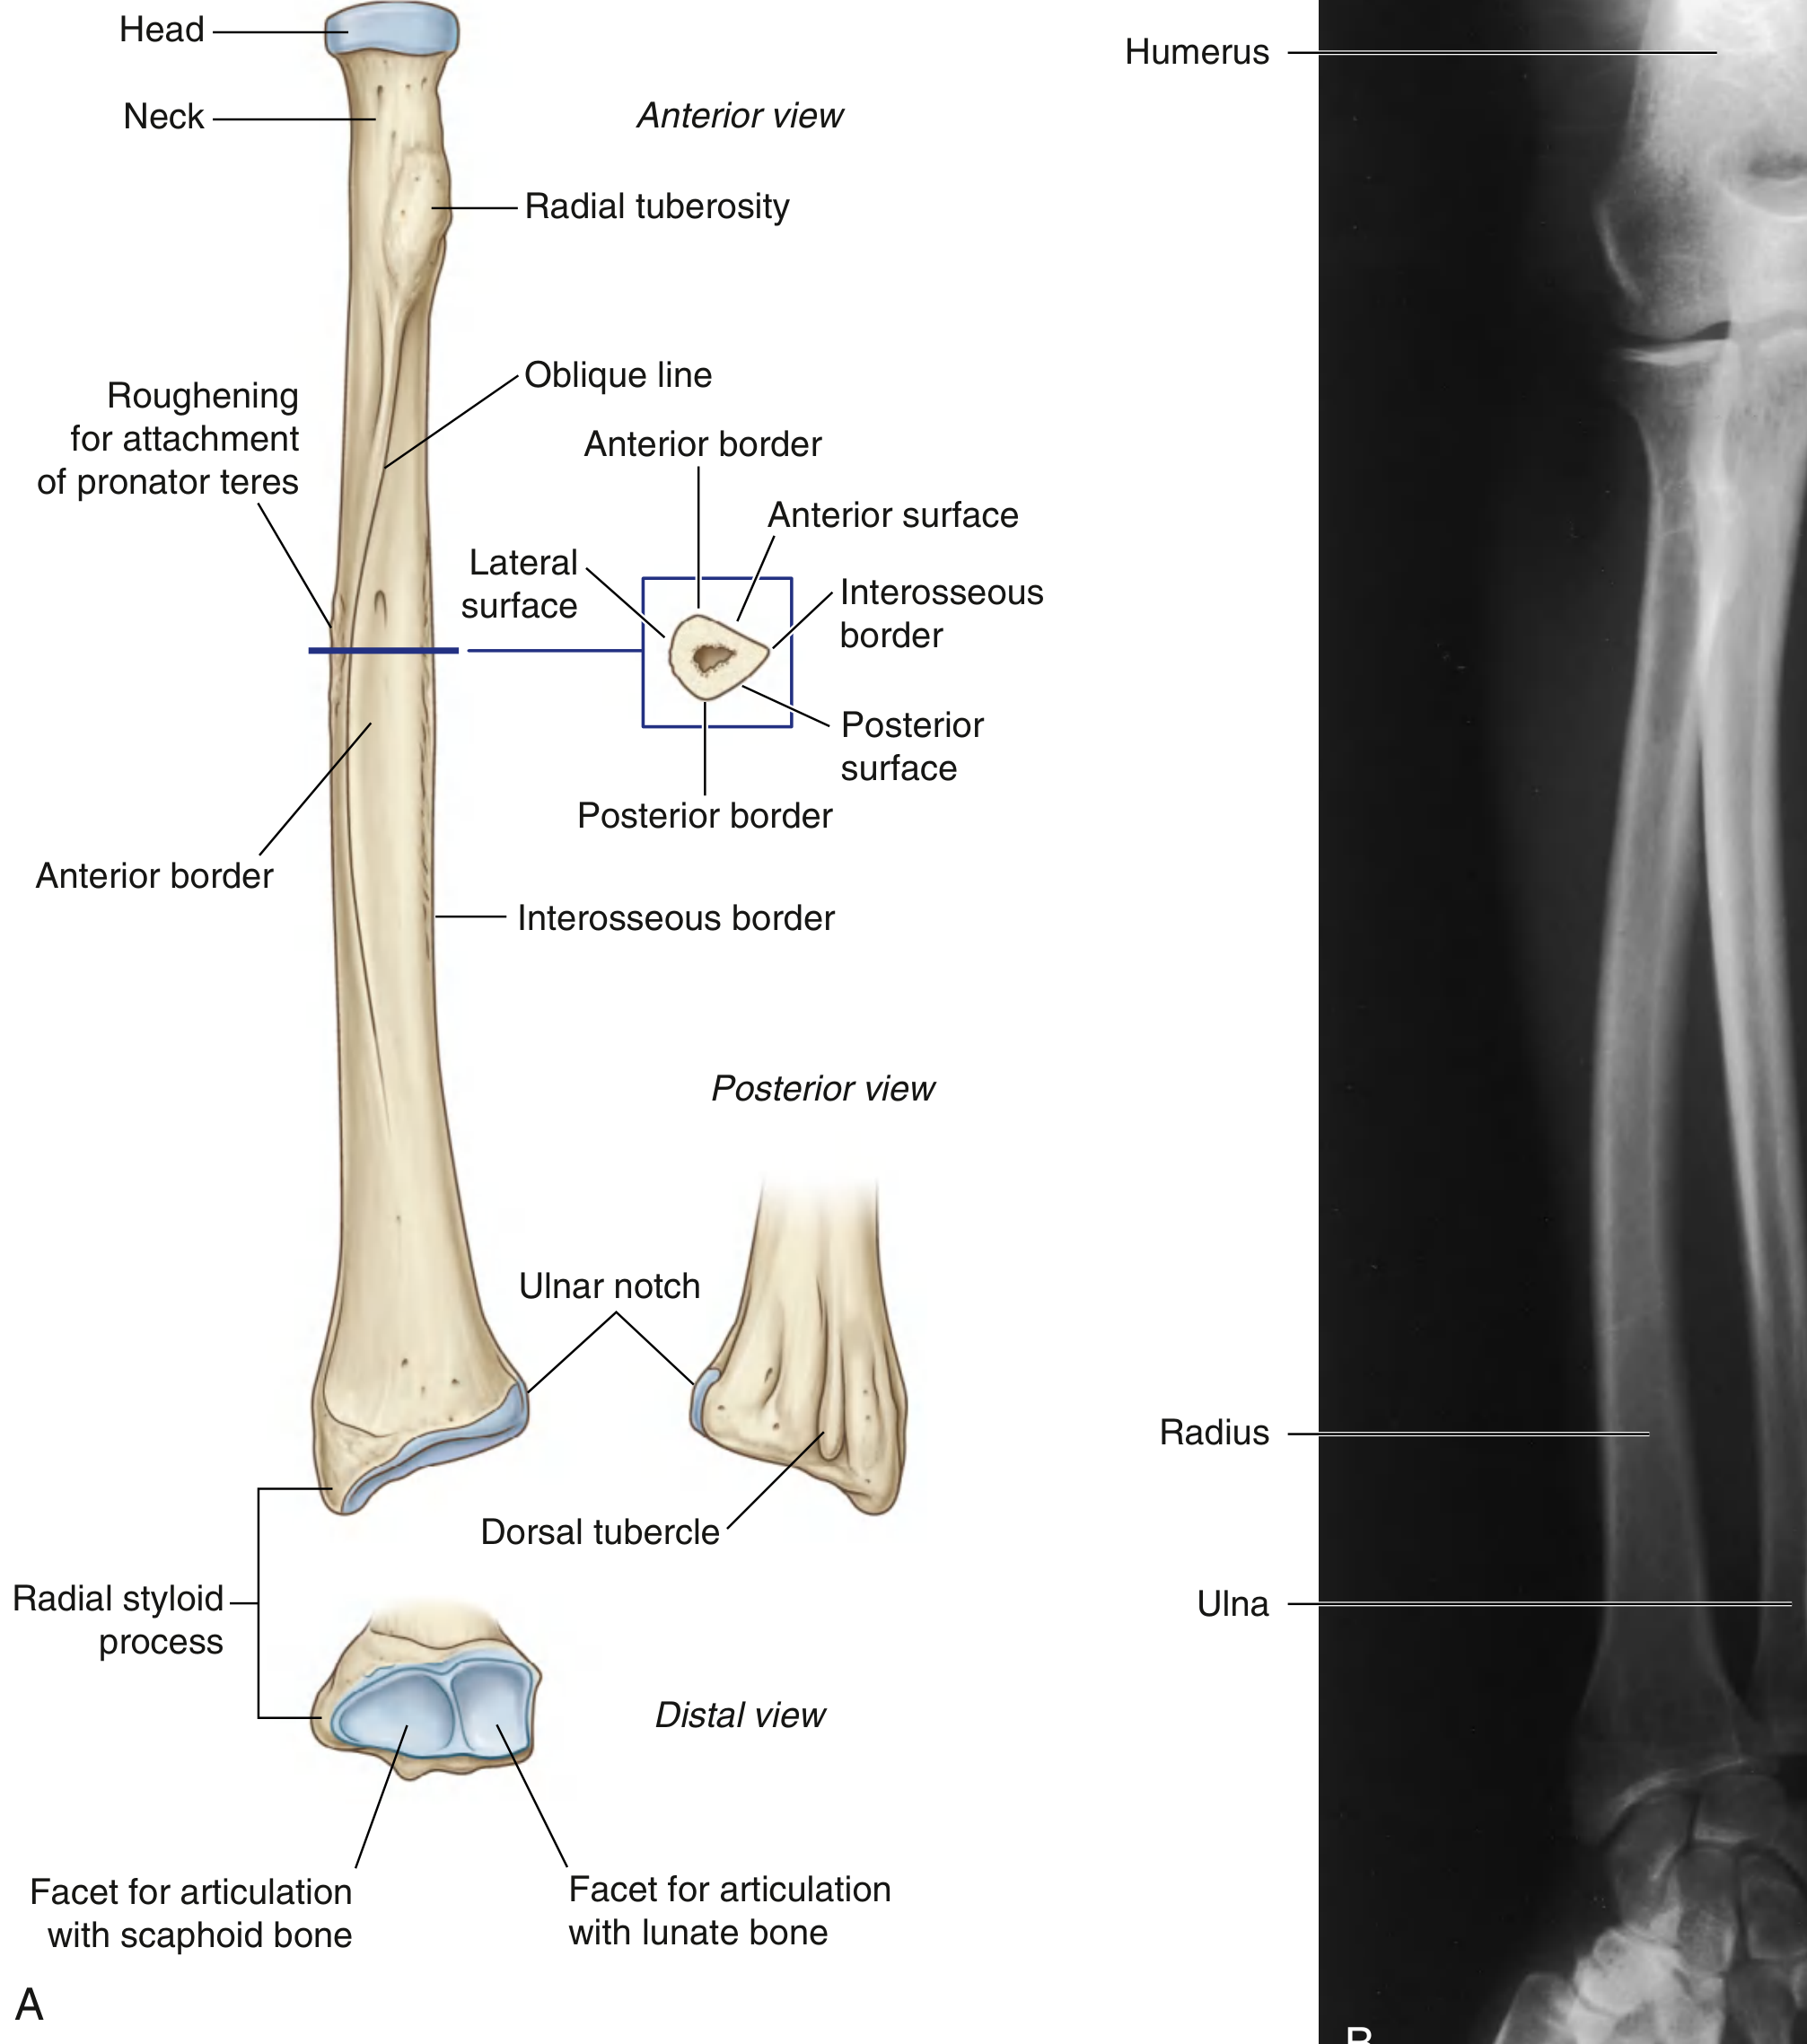

The radius is one of the two forearm bones, located on the thumb (lateral) side.

Complete anatomy of the radius (quick full summary)

• Type: Long bone

• Position: Lateral forearm (anatomical position)

• Shape pattern:

• Small proximally

• Broad distally (forms most of wrist articulation)

Parts

1. Proximal end

• Head of radius: disc-shaped; superior fovea articulates with capitulum of humerus

• Neck of radius

• Radial tuberosity: insertion of biceps brachii tendon

2. Shaft (body)

• Triangular cross-section

• 3 borders: anterior, posterior, interosseous

• 3 surfaces: anterior, posterior, lateral

• Interosseous border gives attachment to interosseous membrane (between radius and ulna)

3. Distal end

• Radial styloid process (lateral)

• Dorsal tubercle (Lister tubercle) posteriorly

• Ulnar notch medially (for distal radioulnar joint)

• Inferior articular facets for scaphoid and lunate (radiocarpal joint)

Major articulations

• Proximal radioulnar joint (with ulna)

• Humeroradial joint (with capitulum)

• Distal radioulnar joint

• Radiocarpal joint (with scaphoid and lunate)

Main functional points

• Essential for pronation-supination of forearm

• Transmits load from hand to elbow

• Distal radius is a common fracture site (for example, Colles fracture)

Labeled radius anatomy

Source: Imaging anatomy text and atlas Volume 3, Bones, joints, Vessels and Nerves, p. 93-95; Gray's Anatomy for Students, p. 892-894.